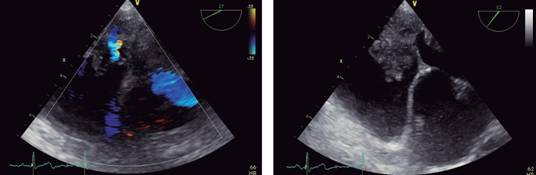

Neurology Department initiated studies to rule out ischemic cerebrovascular disease, with carotid duplex, which was reported as normal; 24-hour Holter monitoring, with sinus rhythm, without evidence of arrhythmias; and a transthoracic echocardiogram was performed finding an intracavitary mass (area 13 cm2, diameters 3.3 × 4.3 cm) that occupied nearly all of the left atrium, echogenic, with a pedicel that originated in the medial part of the interatrial septum and with irregular borders, that moved towards the entry tract of the left ventricle without obstructive phenomenon. Another image was located at the right atrium, of similar characteristics but of smaller size (area 1.4 cm2, diameters 1.7 × 2.4 cm); without being able to determine using this method, if it corresponded to the same mass that went through an interatrial septal defect or if it was independent. No valvular compromise or of the vena cava was observed (Figure 1).

Figure 1: Transthoracic echocardiogram. To the left, parasternal long-axis view where a mass in the left atrium is observed. To the right an apical four- chamber view where a mass that occupies the entire left atrium and partially the right is observed.